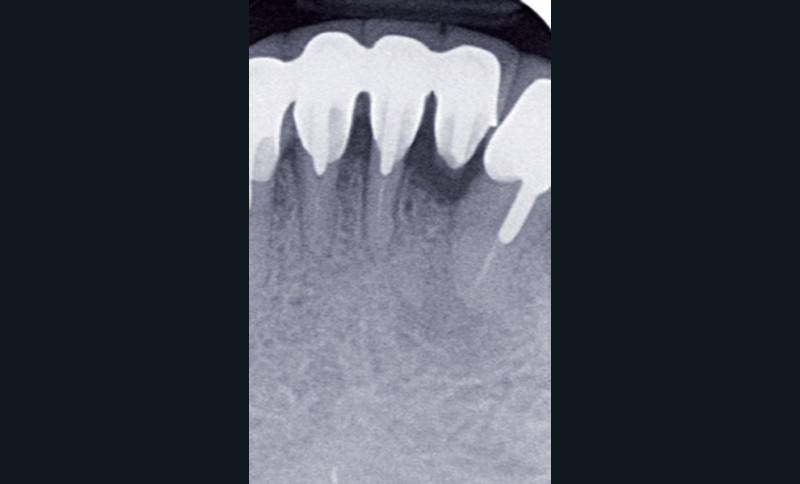

Le contrôle radiologique rétro-alvéolaire montre, quant à lui, une parfaite préservation de l’ostéointégration à 6 ans(fig. 3a et b).